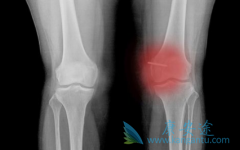

骨 纤维肉瘤 是一种少见的恶性骨肉瘤,也是纤维源性恶性肿瘤。那骨纤维肉瘤与骨恶性纤维组织细胞瘤有什么区别呢?原发性骨纤维肉瘤与溶骨性无结构型MFH影像学改变相近,确诊需依靠组织学检查。骨纤维肉瘤骨质破坏处膨胀不明显,破坏区内有时可见瘤骨及钙 ...